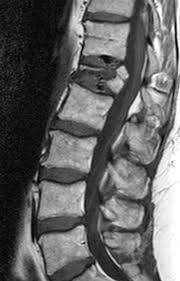

Injury To The Vertebral Endplate Disk Complex Associated With Osteoporotic Vertebral Compression Fractures American Journal Of Neuroradiology

Injury To The Vertebral Endplate Disk Complex Associated With Osteoporotic Vertebral Compression Fractures American Journal Of Neuroradiology from www.ajnr.org